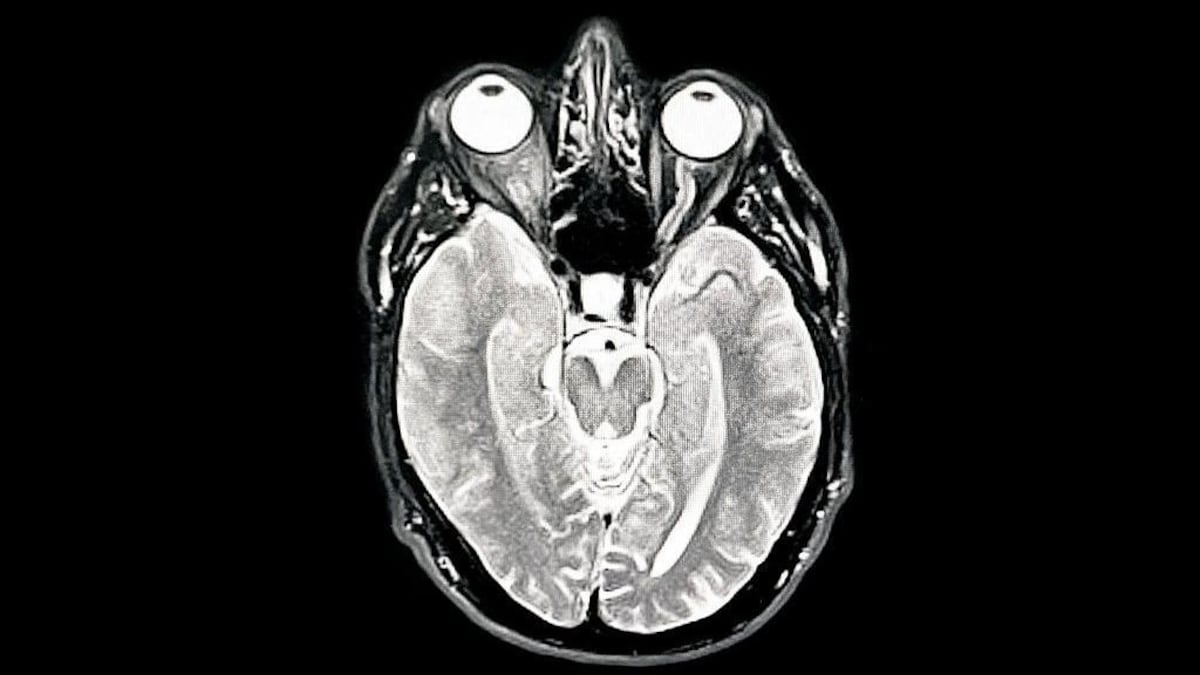

Aunque el estudio analizó cerebros sanos, esta también es la edad en la que comienzan a manifestarse la demencia y la hipertensión, que afectan la salud cerebral.

Una tomografía MIR del cerebro del fotógrafo muestra demencia temprana/Alzheimer / Getty Images